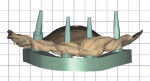

Step 3: The extraoral scan is executed (Figure 6, right). Reverse scan bodies (Straumann® RevEX, Straumann) are attached to the provisional prosthesis, which is scanned extraorally. This scan provides the implant positions for the digital master cast.

The scans taken in steps 1 through 3 were then imported into a computer-aided design (CAD) software (DentalCAD, exocad, exocad.com) and aligned to each other to digitally articulate and cross-mount the STL files (Figure 7). An implant library for the reverse scan bodies was used to inform the software which implants were used for this case and to allow for the connection of the prosthesis to the respective titanium base. To verify that the STL file of the implant positions was accurately captured, a digital technique15 was used to design and mill a verification jig, which was then seated and evaluated intraorally (Figure 8 and Figure 9).